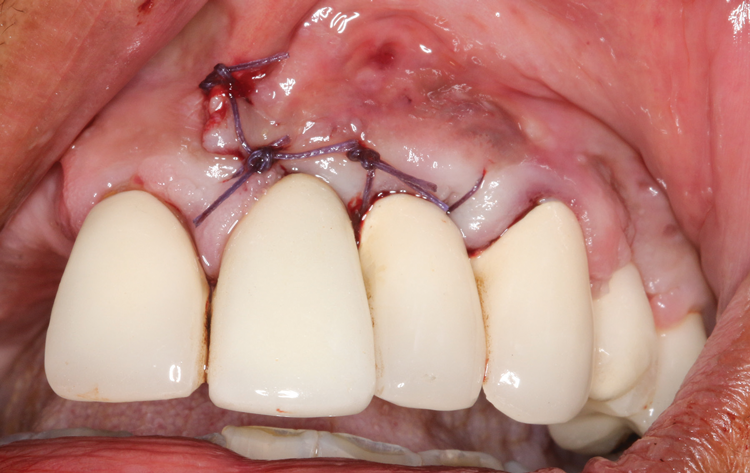

(9.) A sling suture technique was used to reposition and secure the reflected tissue.

Figure 9

(10.) A sling suture technique was used to reposition and secure the reflected tissue.

Figure 10

(11.) A sling suture technique was used to reposition and secure the reflected tissue.

Figure 11

Following infiltration of the facial attached gingiva and palatal area with articaine hydrochloride 4% and epinephrine 1:100,000 (Septocaine®, Septodont [alternatively: Articadent®, Dentsply Sirona; Orabloc®, Pierrel]), an envelope releasing incision was made extending one full tooth over. To prevent trauma to the mucosal tissue, vertical incisions were not made (Figure 3). Incising the mucosa results in the release of prostaglandins and histamine, which increases postoperative discomfort. For this patient, staying in attached gingiva provided excellent control of the flap and allowed clear access to the apical lesion.

There are many grafting materials available today, including allografts (from a human source), xenografts (from another species), and alloplasts (from synthetic materials).23 Following debridement and sterilization of the apical lesion, the site was grafted with a mineralized cortical/cancellous bone allograft material (Newport Biologics Mineralized Cortico/Cancellous Allograft Blend, Glidewell Direct [alternatively: OSSIF-I sem Mineralized Cortical/Cancellous Bone Allograft, Surgical Esthetics; enCore® 50/50 Cortical & Cancellous Allograft, Osteogenics]). The material was packed firmly around the entire implant body but not crushed (Figure 7). Next, a resorbable collagen membrane (Newport Biologics Resorbable Collagen Membrane 3-4, Glidewell Direct [alternatively: Bio-Gide®, Geistlich Biomaterials; BioMend®, Zimmer Biomet]) was trimmed to extend approximately 2-mm beyond the borders of the defect and then passively positioned to serve as a barrier against epithelial growth during the healing and remodeling phase (Figure 8). A sling suture technique using polyglactin 910 suture was then used to reposition the envelope reflection (Figure 9 through Figure 11). Polyglactin 910 suture is a smooth, synthetic, absorbable, braided suture made of polyglycolic acid that is broken down over time by hydrolysis. This suture material reduces the inflammatory response that can be observed with other suture materials.